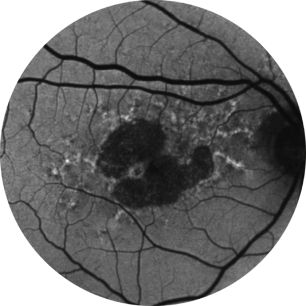

Retinografia de um olho com atrofia geográfica

A atrofia geográfica se caracteriza pela perda progressiva e irreversível dos fotorreceptores, do epitélio pigmentar da retina (EPR) e da coriocapilar subjacente.1,11

As regiões de atrofia normalmente começam fora da fóvea e se expandem para envolvê-la, que, ao longo do tempo, leva à perda permanente da visão.11

Autofluorescência de fundo de olho normal de uma retina

A angiografia por autofluorescência do fundo ocular é, atualmente, uma tecnologia de imagem padrão para visualizar o epitélio pigmentar da retina (EPR) na atrofia geográfica.16